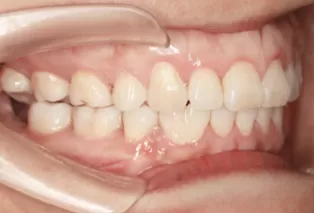

Photos intra-orales après traitement